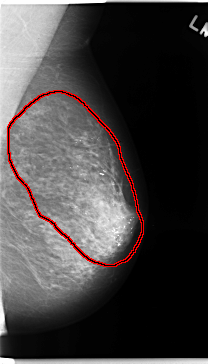

C_0144_1.LEFT_MLO

LEFT_MLO LINES 4720 PIXELS_PER_LINE 2696 BITS_PER_PIXEL 12 RESOLUTION 50 OVERLAY

FILE: C_0144_1.LEFT_MLO.OVERLAY

TOTAL_ABNORMALITIES 1

ABNORMALITY 1

LESION_TYPE CALCIFICATION TYPE FINE_LINEAR_BRANCHING DISTRIBUTION REGIONAL

ASSESSMENT 5

SUBTLETY 5

PATHOLOGY MALIGNANT

TOTAL_OUTLINES 1

BOUNDARY